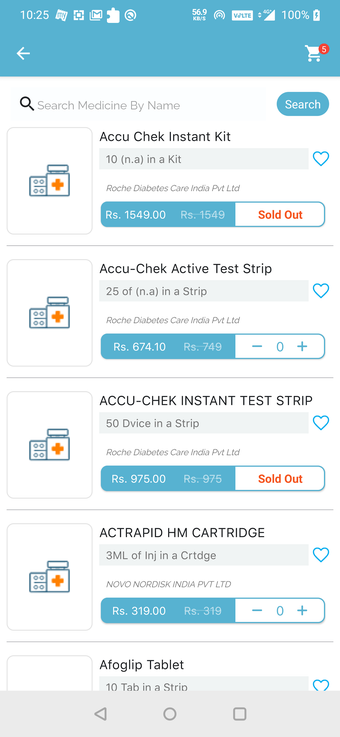

Możesz poprosić ich o wycenę kosztów leczenia lub recepty. Ponadto możesz skorzystać z usług apteki QuickObook. Jeśli pacjent nie ma ubezpieczenia zdrowotnego lub plan ubezpieczenia nie pokrywa kosztów leczenia, zostaniesz o tym poinformowany z góry.